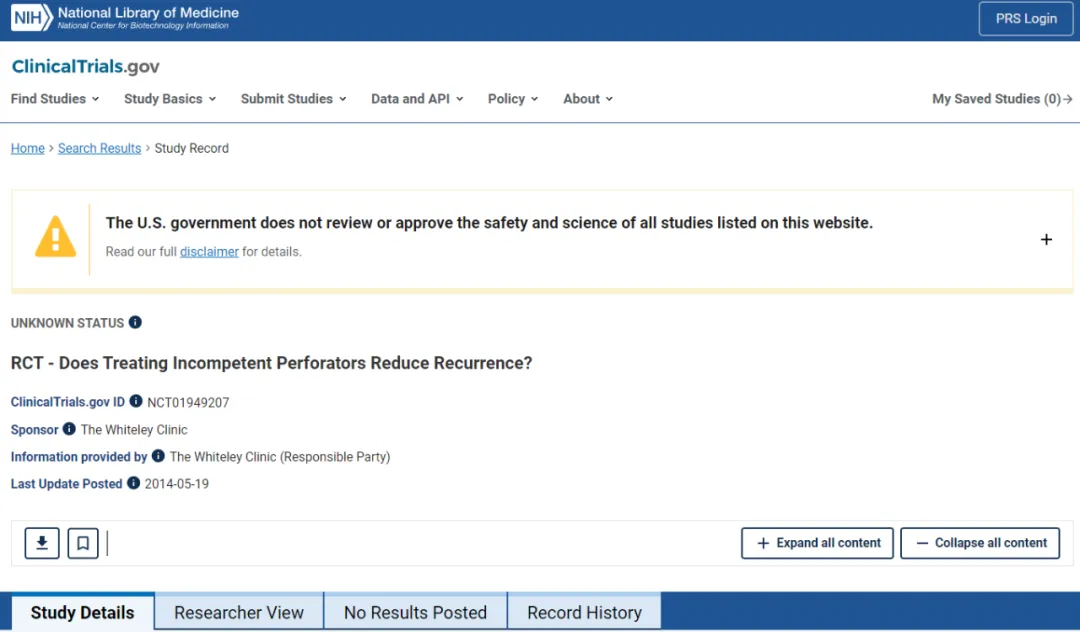

5. 穿支静脉反流 (PVR) 的治疗

许多医生忽略了作为静脉反流模式的一部分的IPV。1985年以前,除了开放结扎术外,没有其他治疗方法。然而,1985年Hauer发明了筋膜下内镜穿支静脉(subfascial endoscopic perforating vein, SEPS)手术,将内镜引入膝下筋膜下间隙,在筋膜下夹闭静脉。然而,SEPS仍需要2 ~ 3 cm的切口,通常需要全身麻醉,术后肌肉操作带来的不适较多,且穿支血管的处理局限在小腿内侧。2000年,发明了经腔穿支静脉闭塞 (TRansluminal Occlusion of Perforators, TRLOP) 手术。

在超声控制下,对IPV进行插管,并在穿支置入消融装置。最初使用射频,后来使用腔内激光。TRLOP在2007年被“重新定义“为“穿支消融术“ (PAPS),尽管两种技术之间没有任何差异。其他工作者通过注射氰基丙烯酸酯胶进一步改进了这一点。TRLOP方法可与这些方法中的任何一种一起用于IPV的局部消融,即使静脉较短。